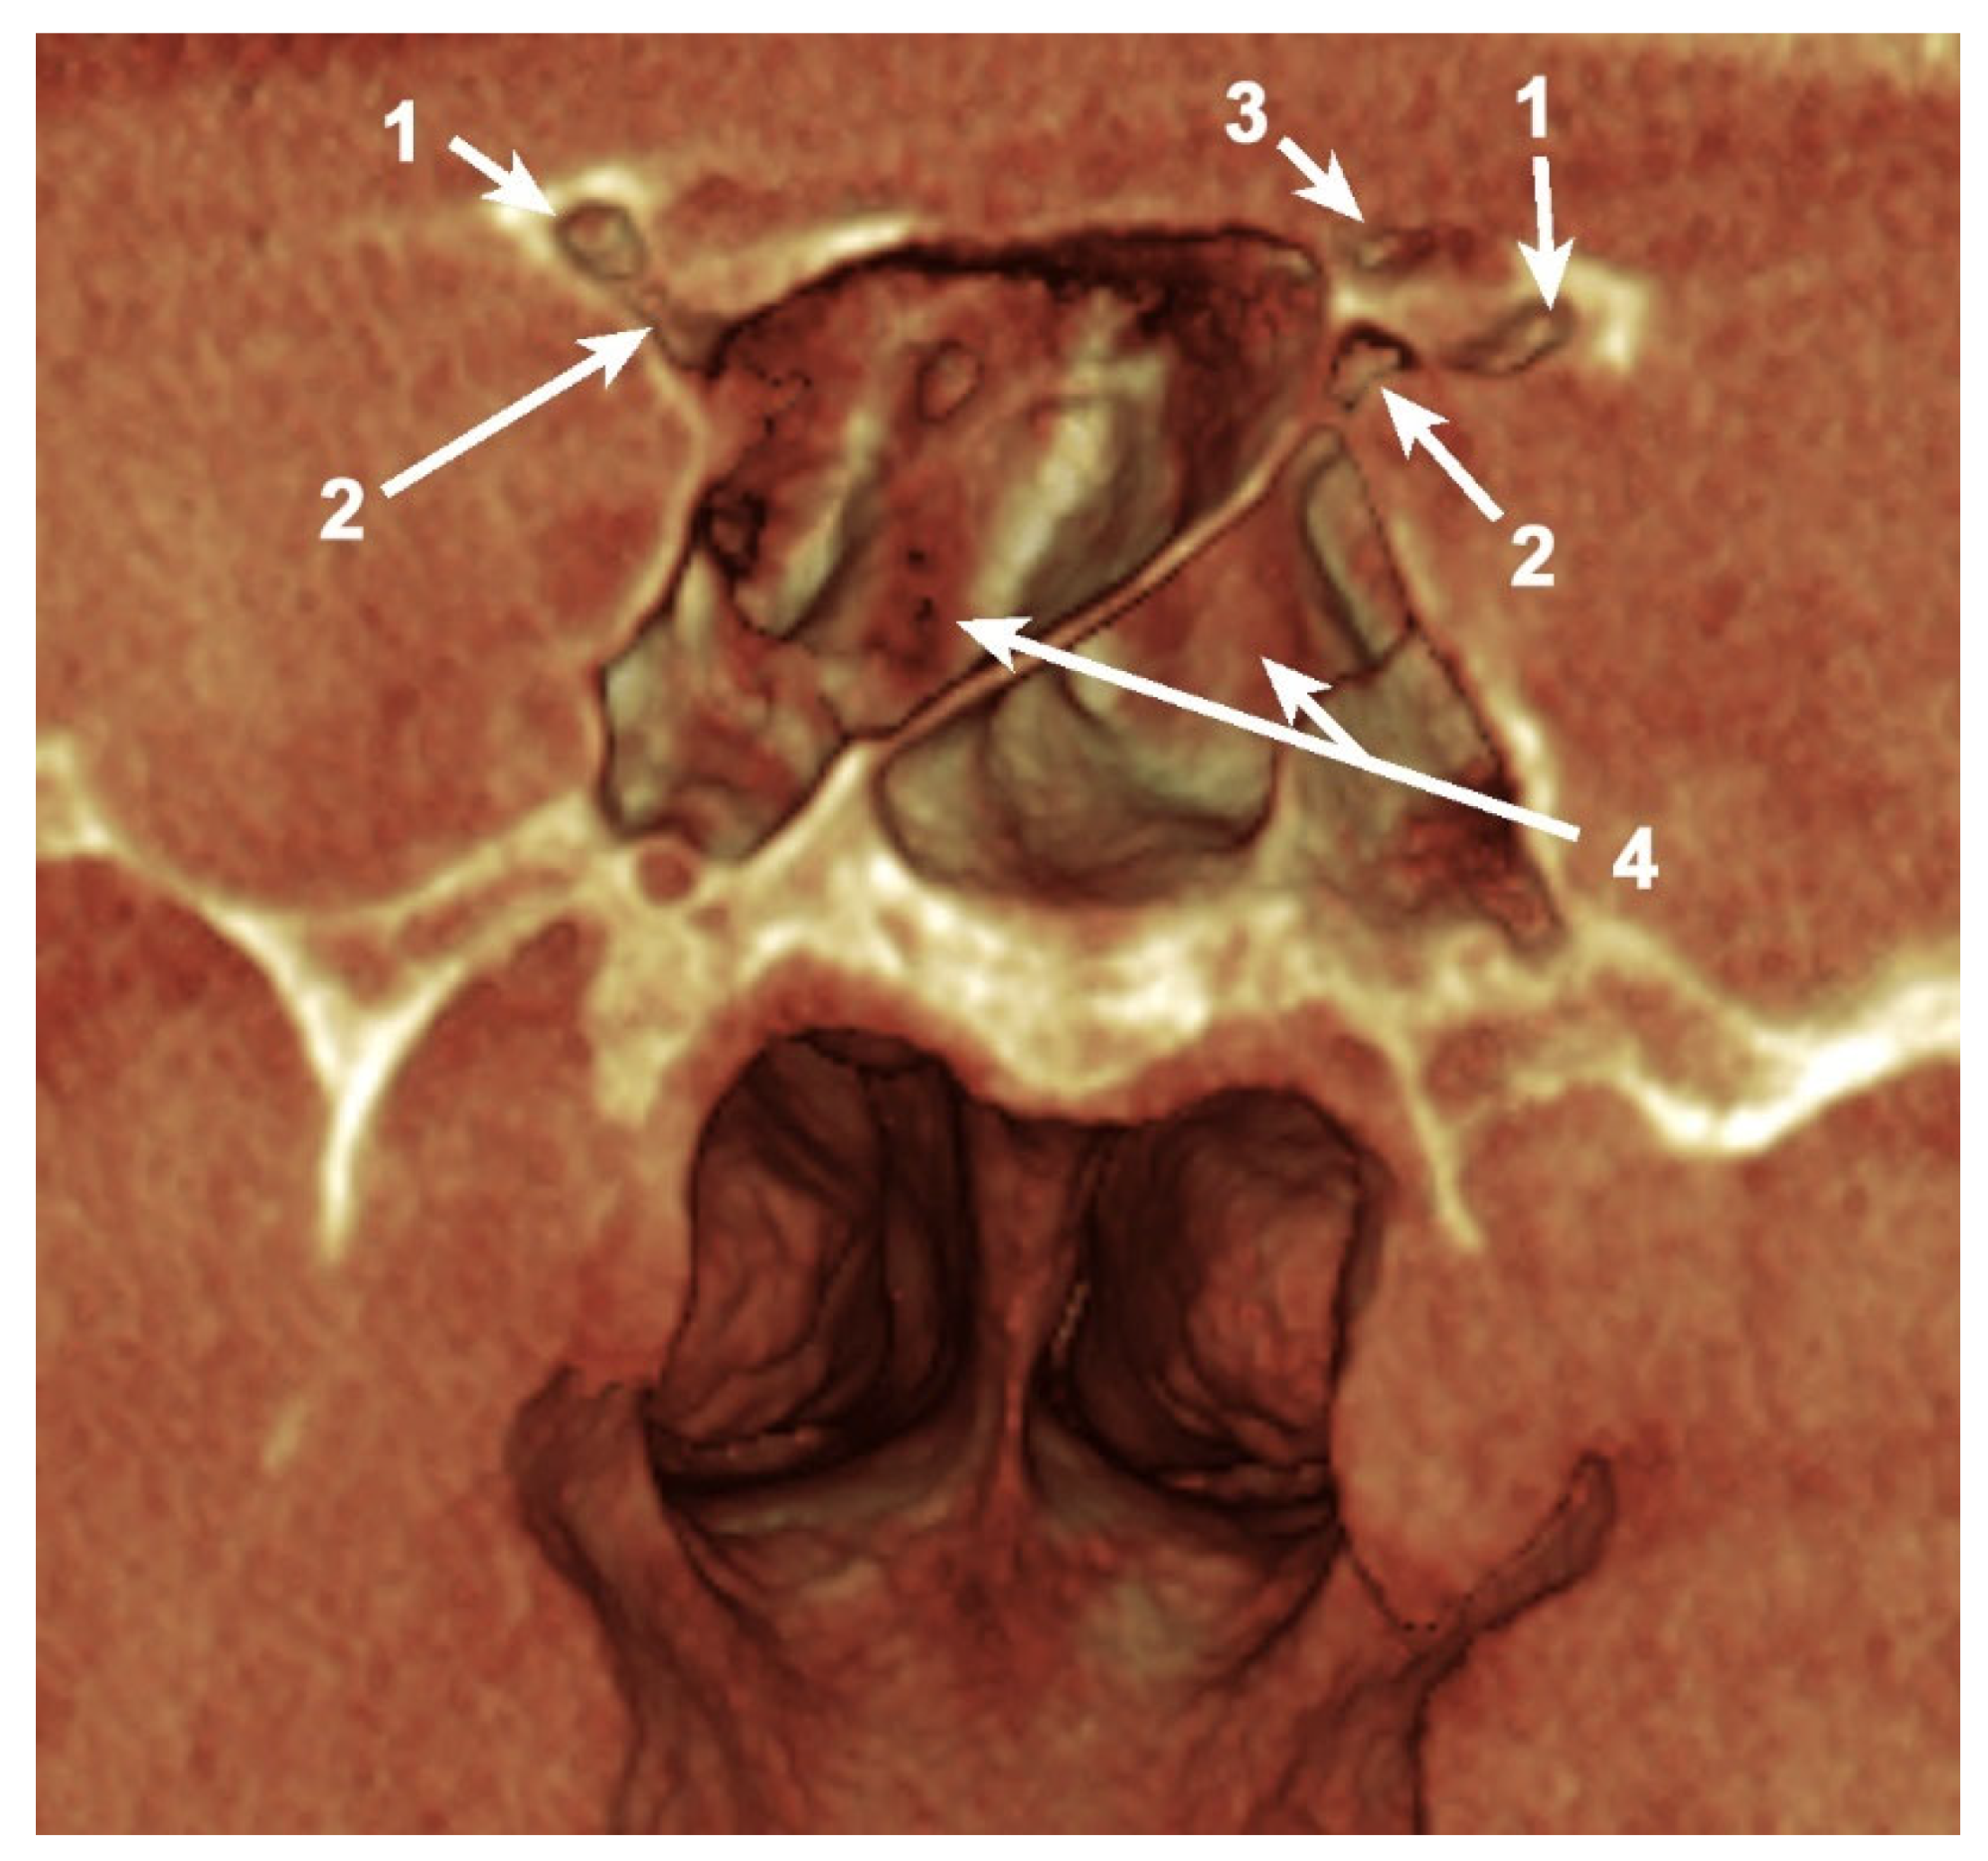

Simultaneous pneumatization of both LSW roots was noted in 31 cases (38.75%) and 43 sides (26.87%) (Table 2; Figure 3). This kind of extensive pneumatization was more frequent in the female group (22 cases, 71%).

Five (16.13%) out of the 31 cases with pneumatization of both LSW roots presented combined pneumatization. If, for the other cases, the origin came either from PEAC (non-ONC/ ONC) or the sphenoid sinus, in these 5 cases, the simultaneous pneumatization occurred from separated origins for each of the two (Figure 3). Two of these patients presented the ONC extending into the OS and the sphenoidal sinus within AR, and the other three cases presented ONC pneumatization extended within the AR and the sphenoidal sinus with a recess within the OS.

Figure 3. Bilateral sagittal CBCT reconstruction, demonstrating the pattern of pneumatization of both the optic strut (OS) and anterior root (AR). (a) Left side; (b) Right side: 1. Pneumatized AR; 2. Pneumatized OS; 3. Onodi cell; 4. Sphenoid sinus.